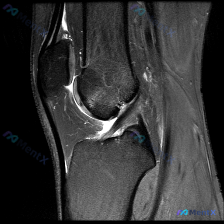

给大家分享一份最近遇到的踝关节MRI读片病例,初始问题指向软骨异常,整理一下完整的分析思路,一起讨论。 一、病例影像基本信息 这是一份踝关节矢状位T2加权MRI图像,图像质量好,信噪比高,解剖结构清晰,涵盖了胫骨远端、距骨、跟骨、足舟骨、骰骨及部分跖骨基底部,胫距关节、距下关节、窦跗管、跟腱等关键结...